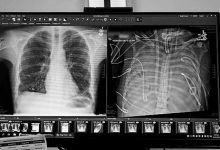

X光片显示的一名33岁患者的新肺(左)和旧肺。 本报讯 一名33岁的男子在没有肺的情况下存活了48小时。一个医疗团队用一套体外人工肺系统维持了这名男子的生命,直到他接受了双肺移植手术。1月30日,相关研究结果发表于《医学》。 过去有一些病例...